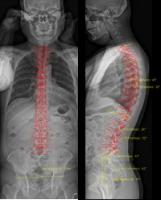

正面と側面の二方向から同時にX線を照射して撮影し、脊椎や股関節の形体、配列の評価を行う検査です。

立位または座位で撮影するため、椎体や関節に体重がかかった状態での骨格の全体像を観察することができます。

脊椎変形や側弯症、変形性膝関節症、変形性股関節症の評価に役立っています。

画像解析により、脊椎のカーブの角度や、股関節の高さの左右差を、数値で評価することができます。